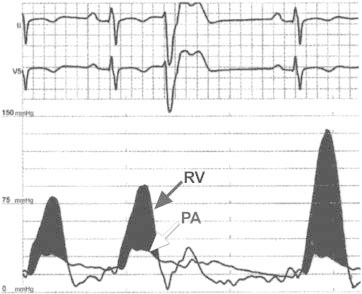

Angiography was performed to measure and characterize the gradient across the RVOT. There was a hemodynamically significant gradient of 54 mmHg (mean, 33 mmHg). When the patient coughed and then performed the Valsalva maneuver, the peak gradients increased to 94 mmHg and 106 mmHg, respectively. Potentiation of the peak gradient across the RVOT was observed after a premature ventricular contraction (Fig. 7). Because of the patient's unexplained syncope, a cardioverter-defibrillator was implanted for the primary prevention of sudden cardiac death. An atrial lead was also implanted to accommodate any future need for atrioventricular synchronous pacing. Transthoracic echocardiography was performed to evaluate the effect of RV pacing on the RVOT gradient. The peak gradient across the RVOT was 17 mmHg with RV pacing and 37 mmHg without RV pacing (Fig. 8).

Fig. 7 Hemodynamic tracings from right-sided heart catheterization show simultaneous right ventricular (RV) pressure (across the RV outflow tract) and pulmonary artery (PA) tracings. This figure shows potentiation of the peak RV gradient (bottom tracing) after a premature ventricular contraction.